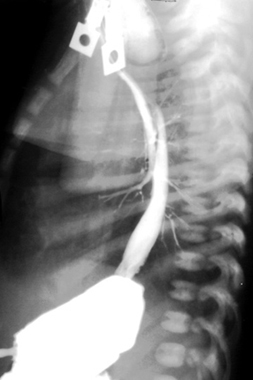

| While one would not purposely perform a study in this way, it nicely demonstrates the anatomy of esophageal atresia with TE fistula. Contrast was administered through a G tube into the stomach. The contrast refluxed into the distal esophagus across the tracheoesophageal fistula into the trachea and from the trachea into the esophageal pouch. |